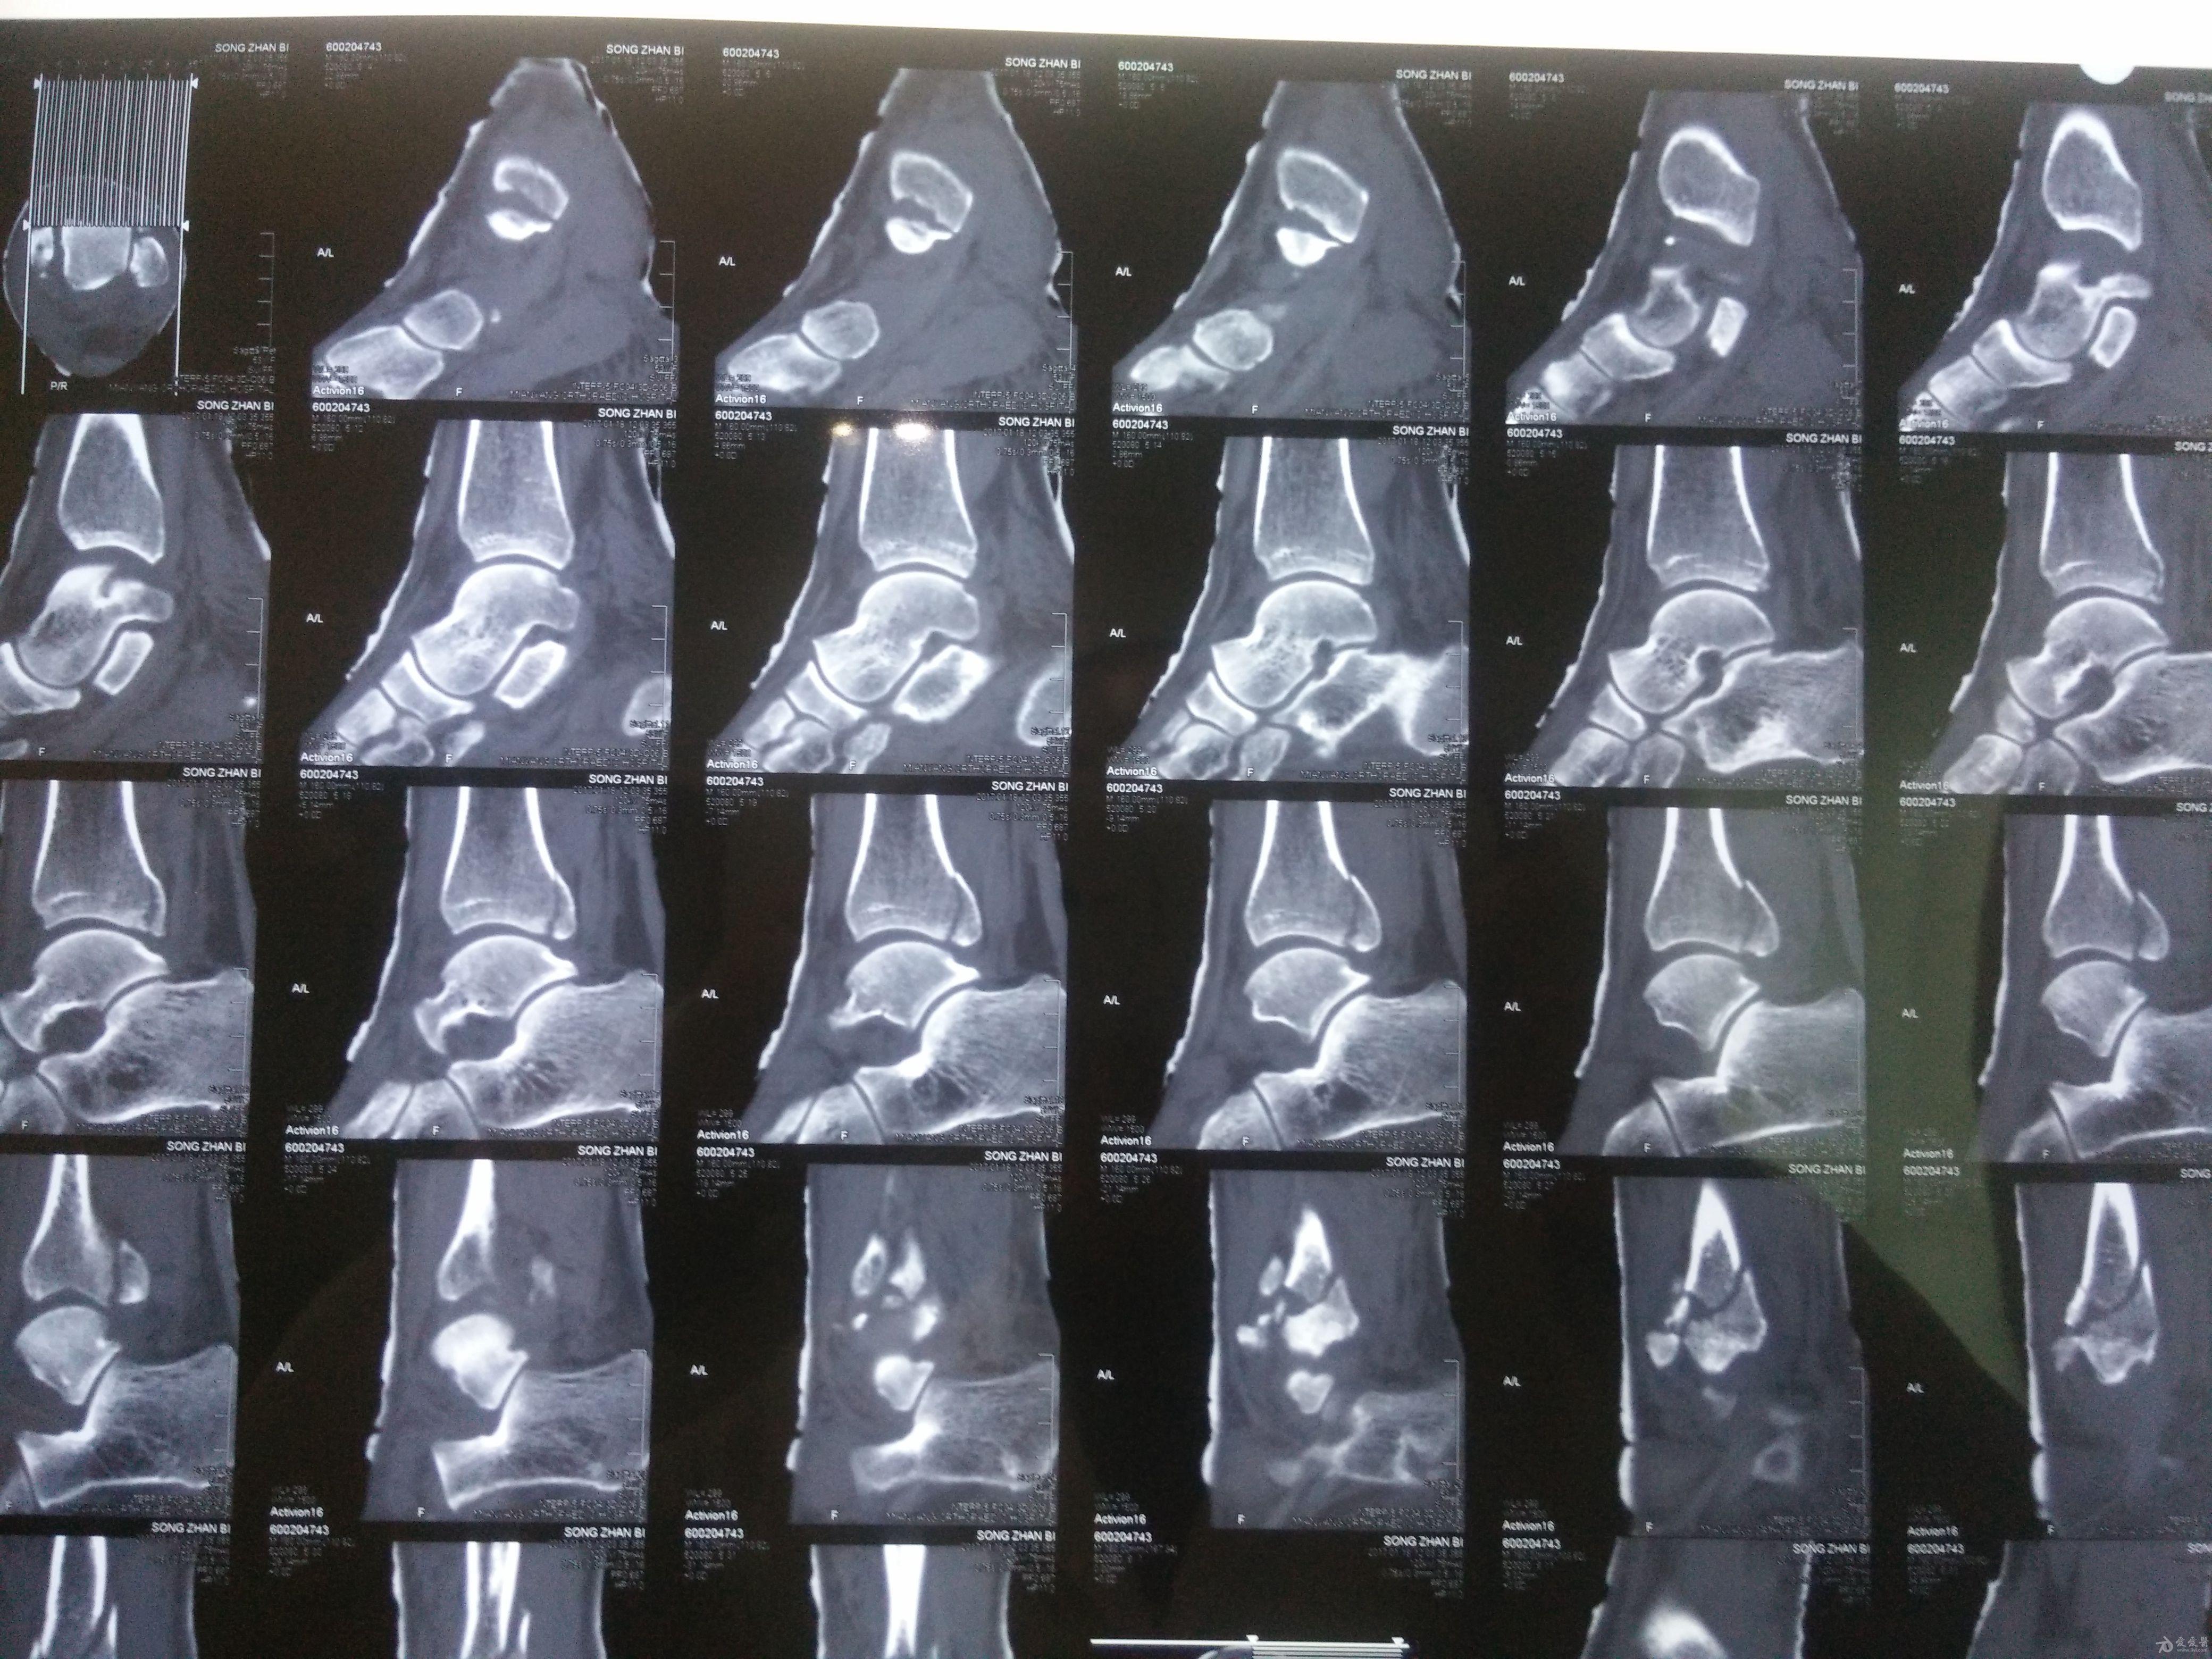

左三踝骨折手术治疗

患者女,外伤后左踝关节活动受限1小时入院,

入院后查体:左踝关节肿胀,活动受限,行DR及左踝关节CT检查,如下图,手术待肿胀消退后行手术治疗,目前愈合良好,请问问各位老师,好久可以下地呀, 下胫腓联合镙钉3个月取呀,

这个下胫腓螺钉真的没有必要打,另外后踝的两枚螺钉怪怪的,从后往前打的,看着钉子帽偏内侧,这个应该在外侧才对,